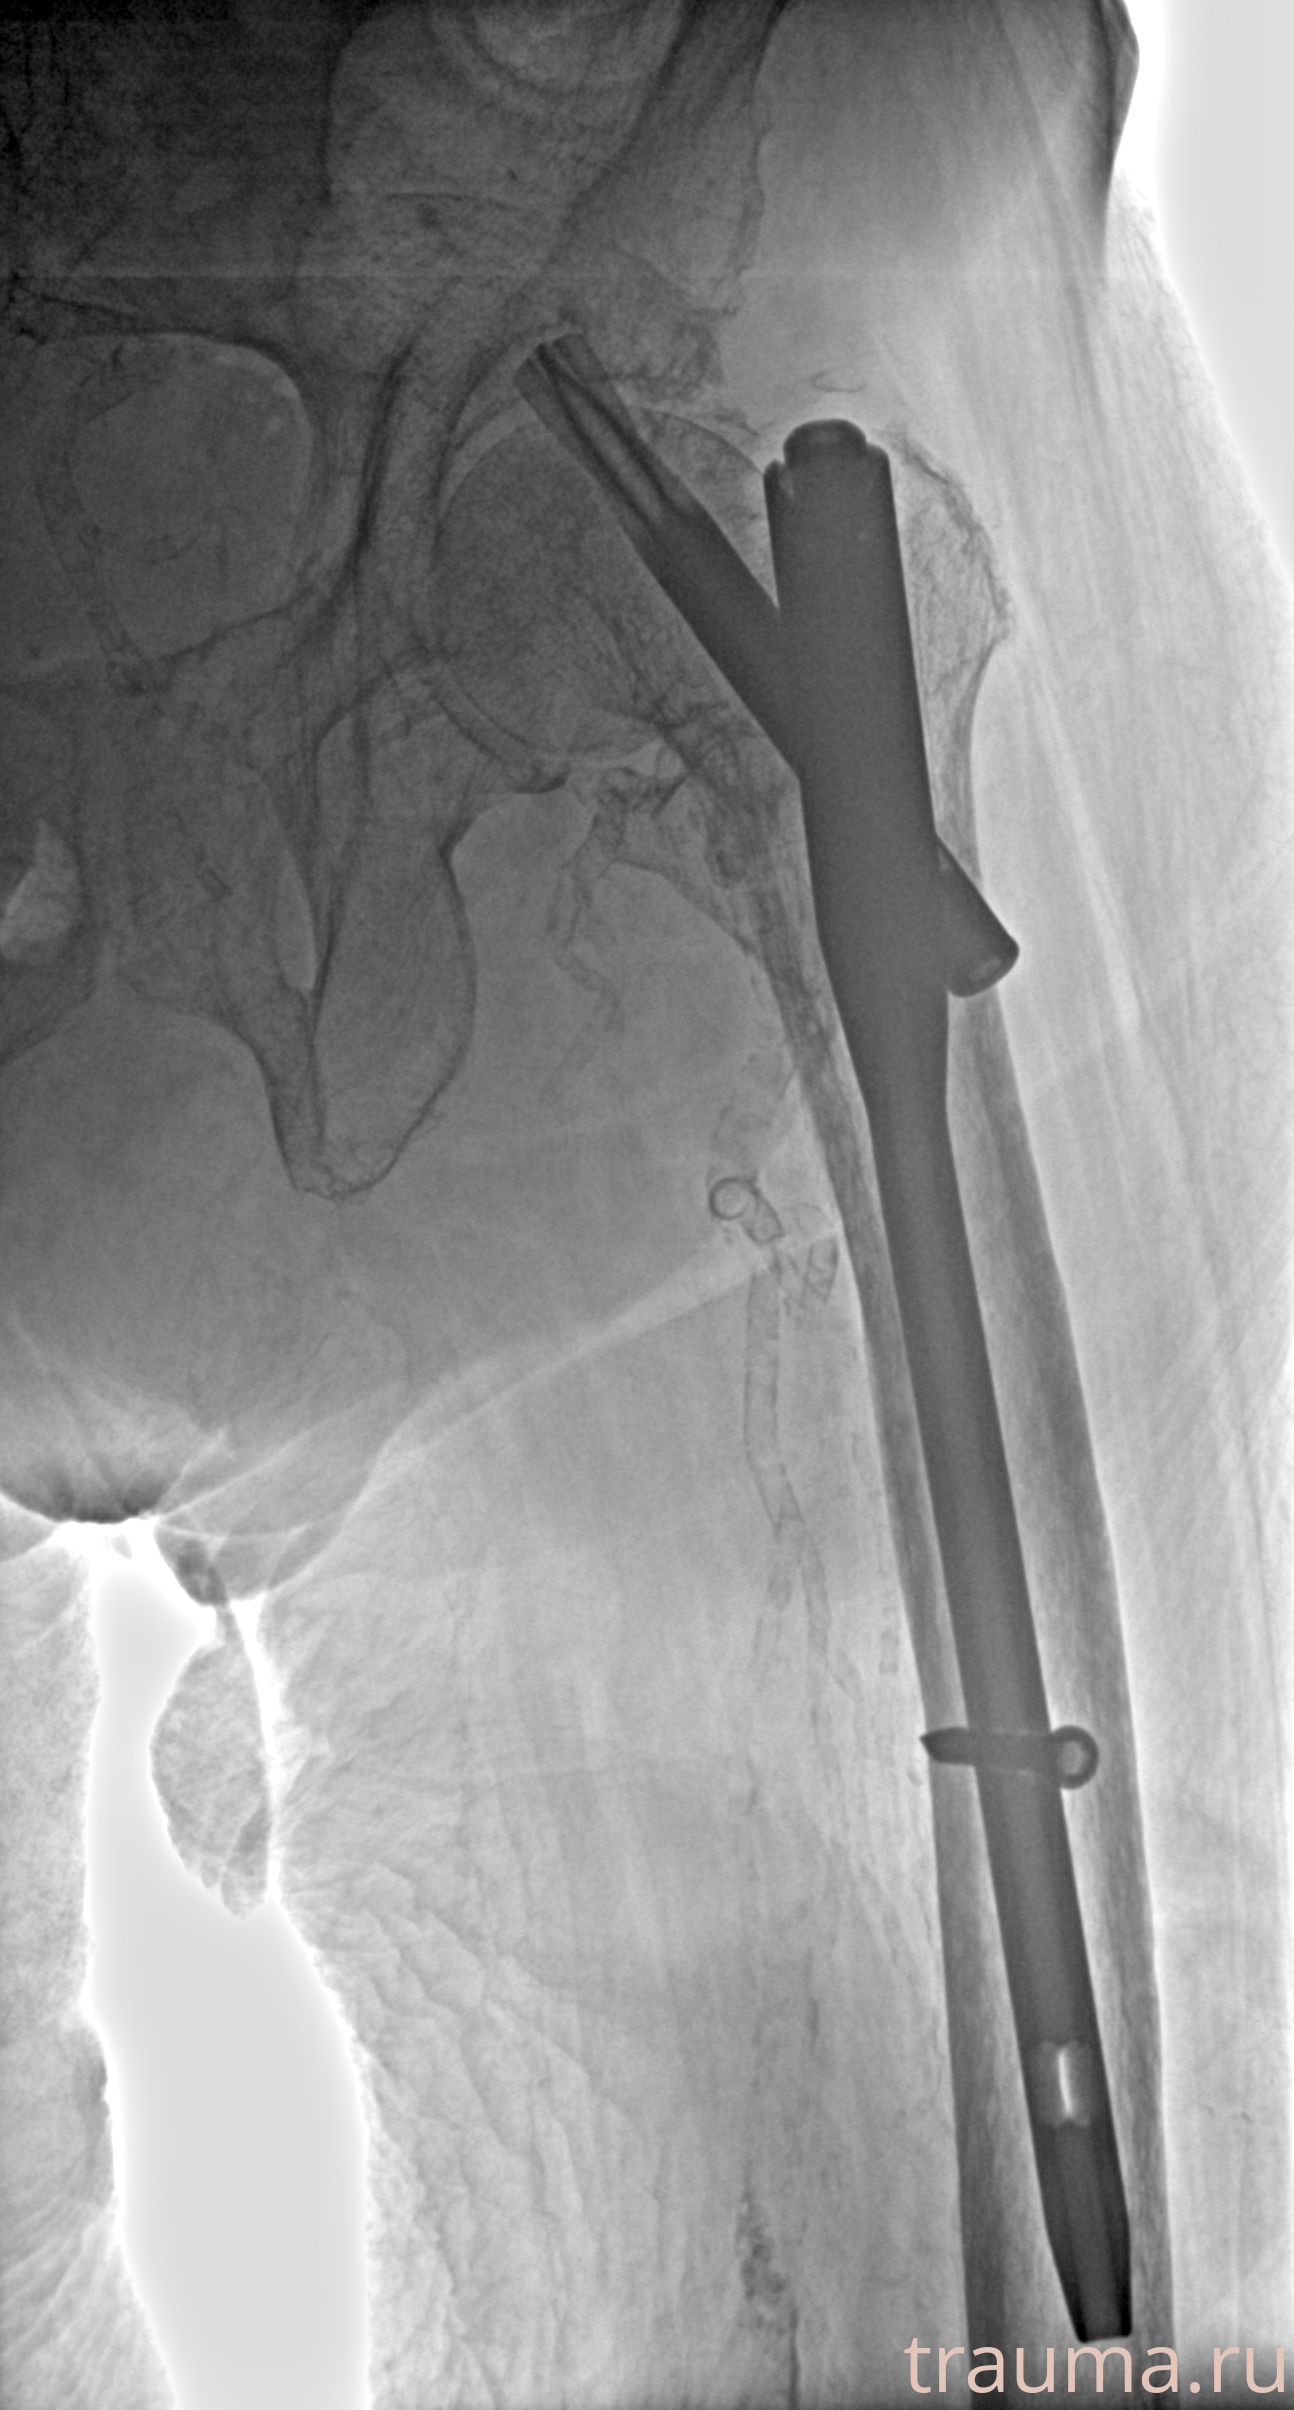

Рентгенограммы

Рентген на дому: по вашему адресу приезжает врач-рентгенолог, травматолог-ортопед с мобильным рентгеновским аппаратом, проводит диагностику травмы или заболевания, делает необходимые рентгенограммы, дает рекомендации по дальнейшему лечению. Получить качественные снимки в домашних условиях возможно благодаря уникальной методике, разработанной МосРентген Центром для института  Склифосовского